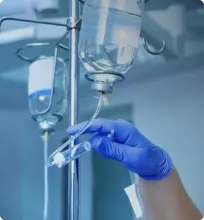

Попытки совершения самоубийства являются прямым показанием для госпитализации. В наркологическая помощье психиатрии «Наше здоровье» в Людиново есть специальный стационар, где пациент, склонный к суициду, будет находиться под круглосуточным наблюдением персонала. Для больных, проходящих курс лечения в нашем наркологическая помощье, созданы приближённые к домашним условия, что способствует ускорению выздоровления.

Главным препятствием для терапии суицидального поведения становится отказ больного ложиться в клинику для прохождения курса лечения. В этом случае вызывайте скорую психиатрическую помощь без предупреждения. Наши психотерапевты имеют большой опыт убеждения таких пациентов. Это законный способ помещения больного без его согласия в стационар и одна из немногих возможностей спасения жизни.

В нашем наркологическая помощье для лечения пациентов, имеющих суицидальные наклонности, применяют эффективные методики психотерапии. Психологическую помощь в нашем наркологическая помощье предоставляют и близким больного. Кроме этого, родственники могут получить бесплатную телефонную консультацию о профилактике суицида.